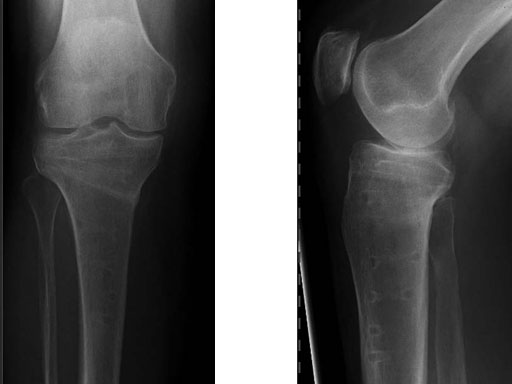

The existing TomoFix medial high tibia (TomoFix MHT) for openwedge osteotomies has been redesigned for better soft-tissue protection and to minimize rotation during compression.

The precontoured plate now has a chamfer at the proximal part and rounded edges at the lateral rims of the plate. A MIPO tapered end at the distal end was added to have a smoother pass to the bone. The two upper LCP holes in the distal part were slightly repositioned in line with the axis of the plate to eliminate the rotation of the plate during compression with cortex screws because of the former asymmetrical alignment of the holes. The two most distal LCP holes were changed to isolated LCP holes to hinder the use of cortex screws.

In a biomechanical comparison, the plates were tested after a right osteotomy. The results show a higher number of cycles with the new TomoFix MHT due to improvements in the manufacturing process. The quality of bone healing with the new TomoFix MHT is similar to the former one but the healing time is expected to be faster and insertion easier. The less prominent design reduces the pain and the higher stiffness activates the use of the compression screw. Handling, use, hospitalizations time, and all other biomechanical characteristics are comparable with the former plate.